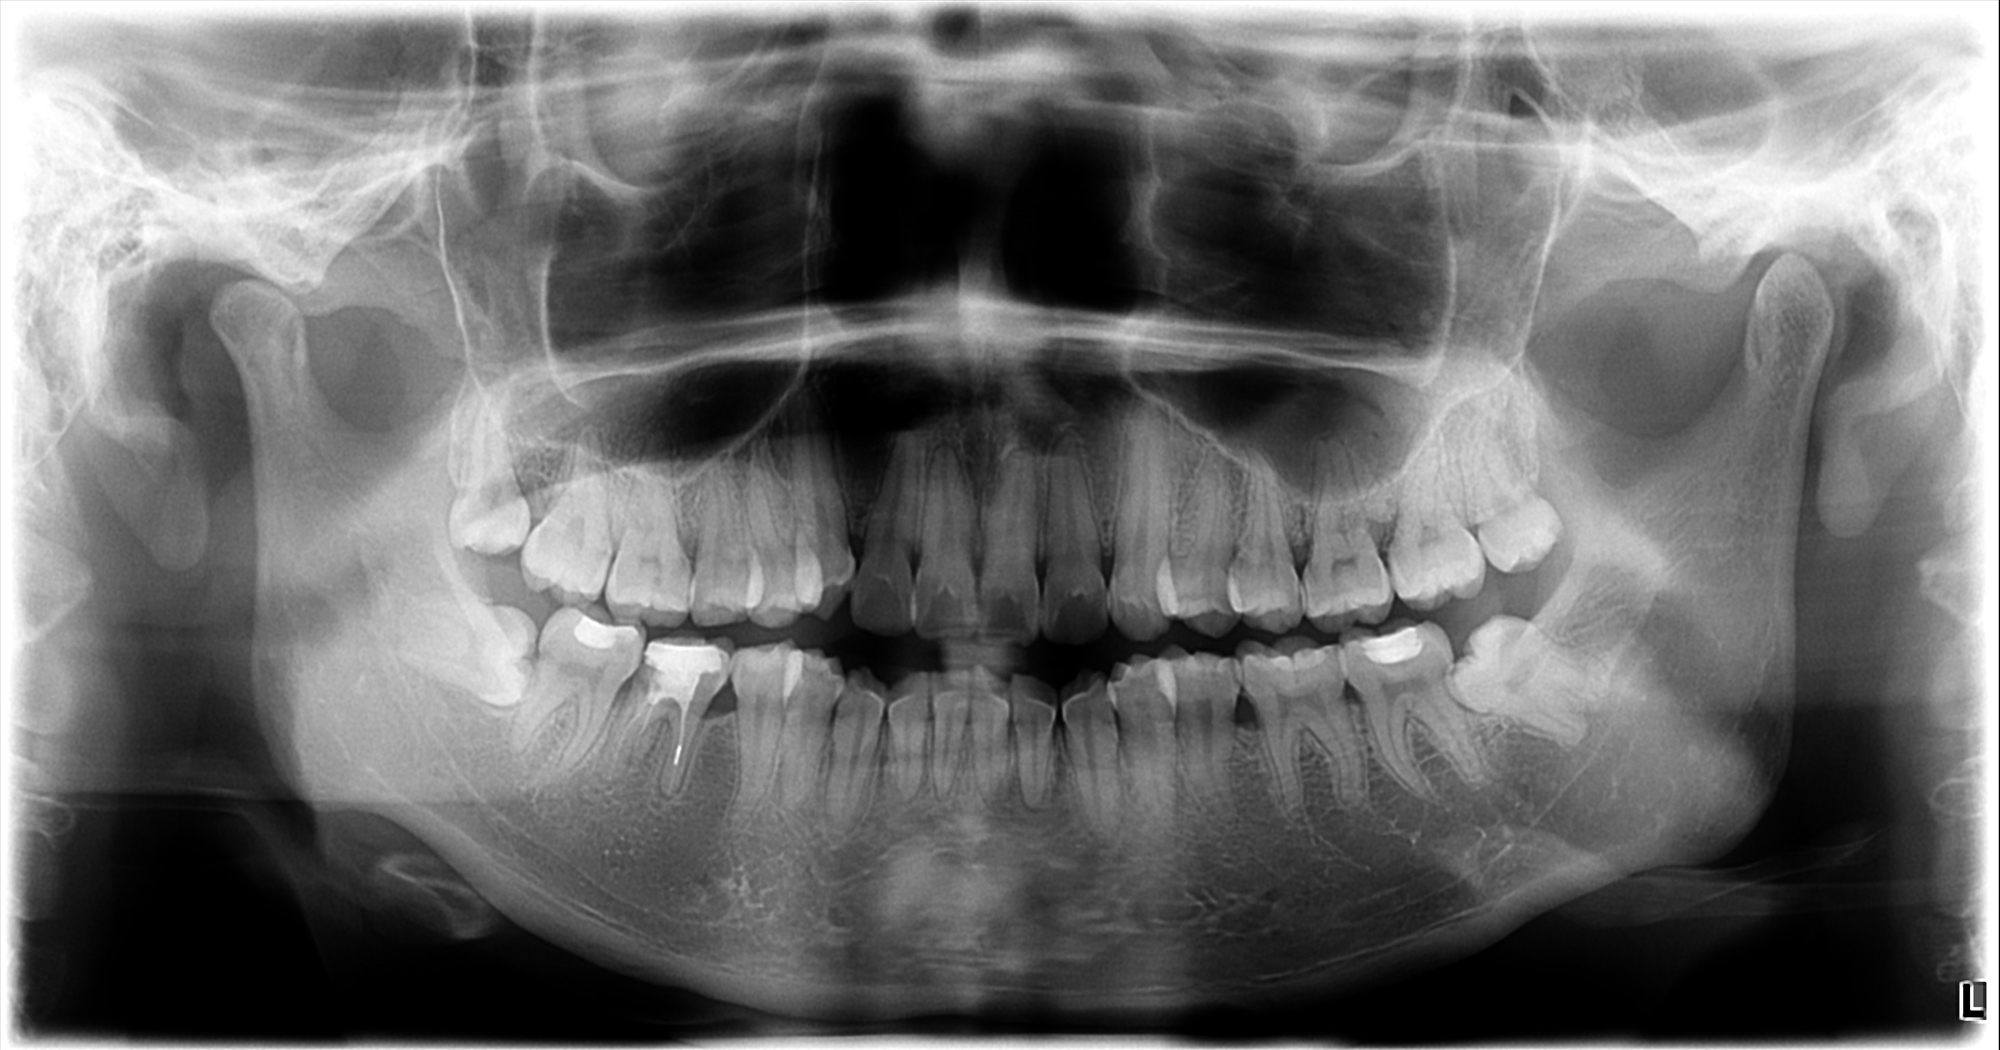

初步沟通后拍X光牙齿及头部骨头照片,拍片的目的是为了看你的牙齿及骨骼发展方向等,以利于以后制定准确的矫正方法。